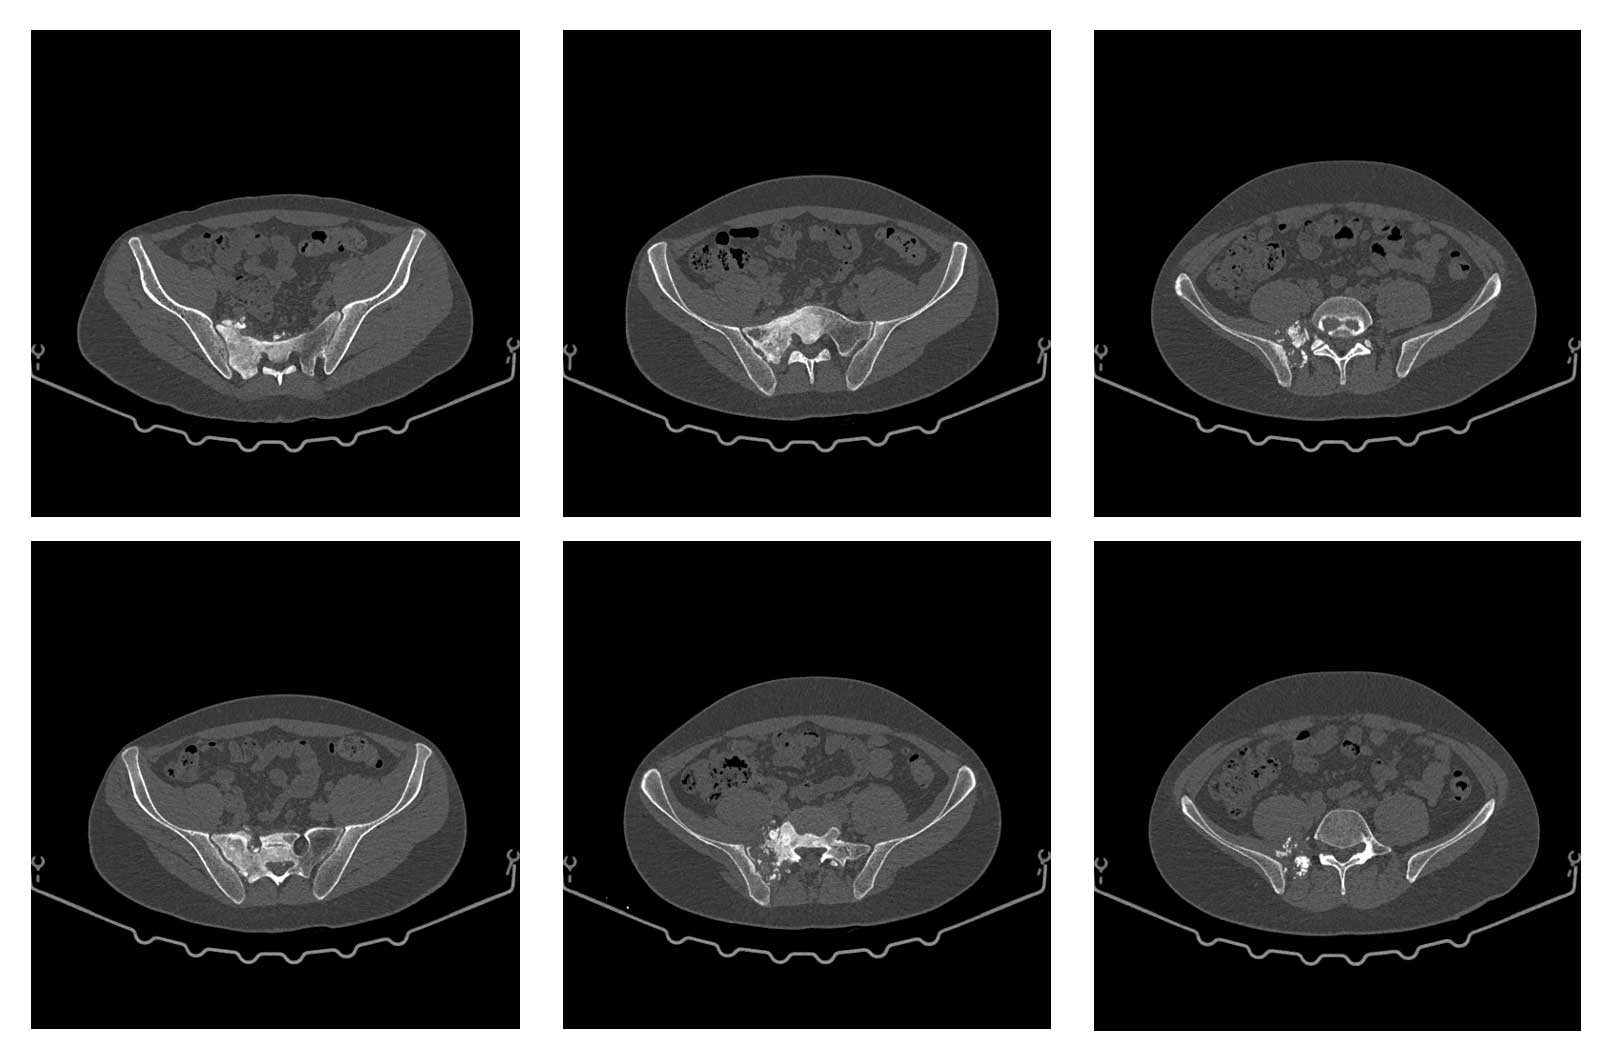

Ameliyat Öncesi: Tomografide sağ sakroiliak bölgede düzensizlik ve sklerozun eşlik ettiği tümör dokusu görülmekte.